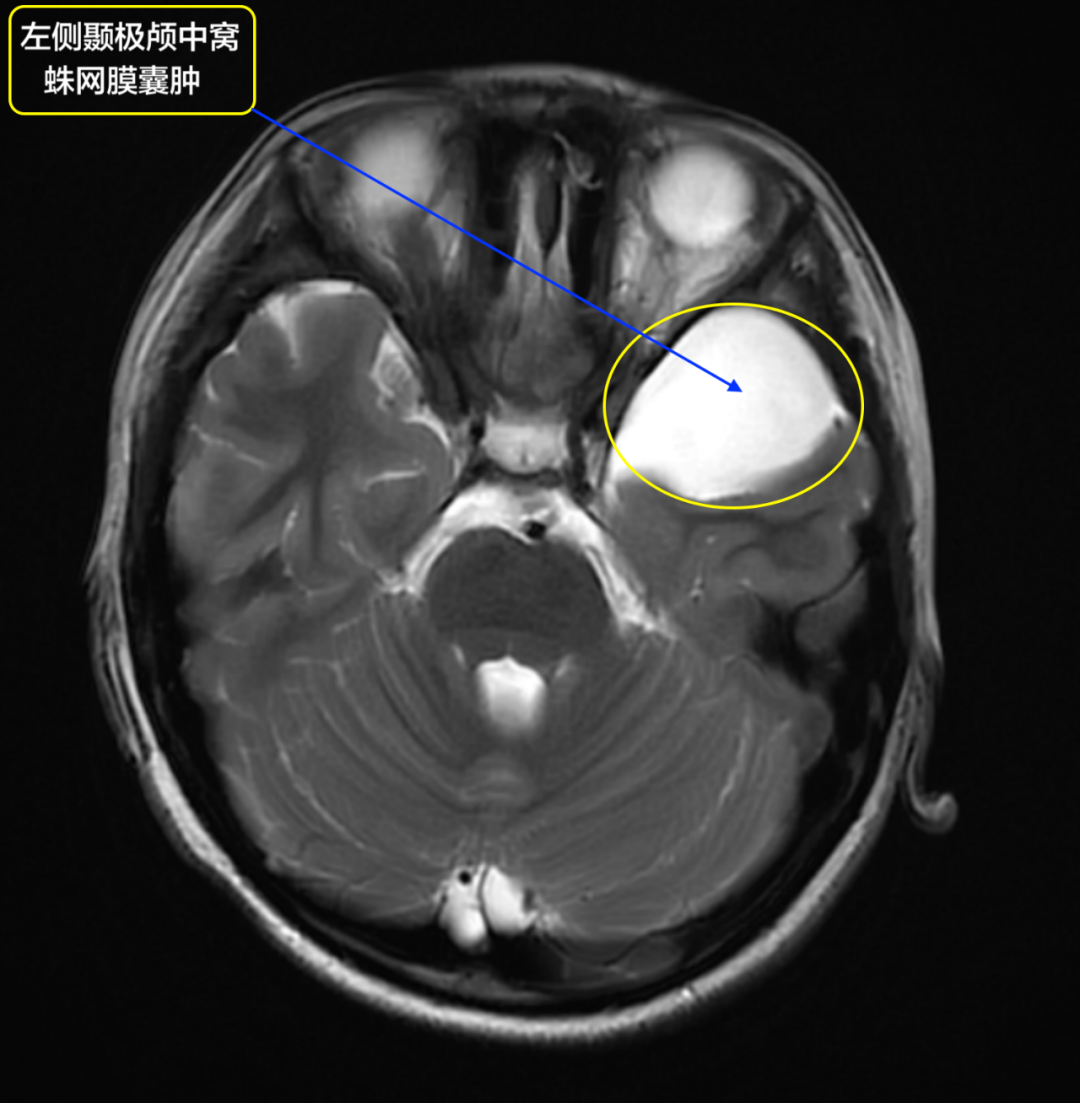

蛛网膜囊肿

估计很多朋友在做ct,mri时发现了蛛网膜囊肿,小可以根本不用理会

一网打尽颅内非肿瘤性囊肿!